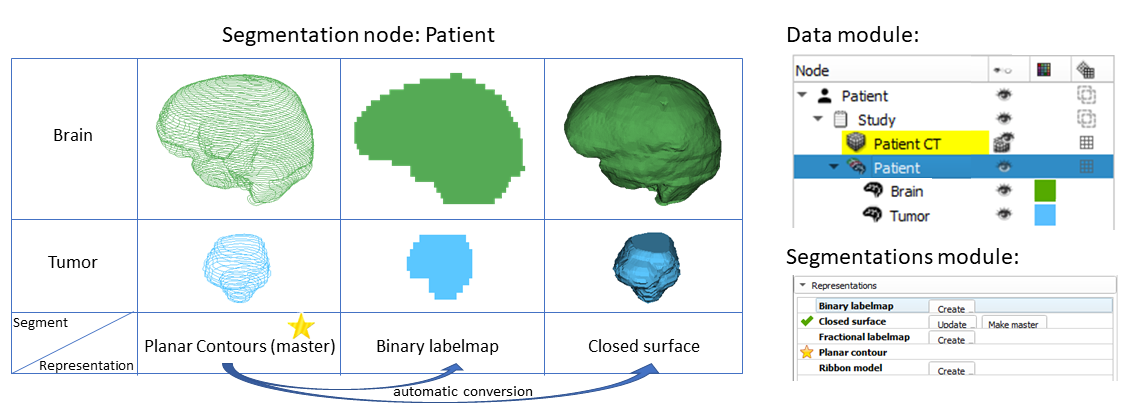

分割的结果存储在3D Slicer中的segmentation节点中。一个分割节点由多个段组成。

一个段指定单个结构的区域。每个段都有许多属性,如名称、首选显示颜色、内容描述(能够存储标准DICOM编码条目)和自定义属性。段可以在空间上相互重叠。

一个区域可以用不同的方式表示,例如作为二进制标签图(每个体素的值指定该体素是在区域内还是区域外)或闭合表面(表面网格定义区域的边界)。没有一种表示方式适用于所有情况:每种表示方式都有其优缺点,并根据需要使用。

每个段存储在多个表示中。一个表示被指定为源表示(在用户界面上标有“金星”)。源表示是唯一可编辑的表示,它是保存到文件时唯一存储的表示,所有其他表示都是从它自动计算的。